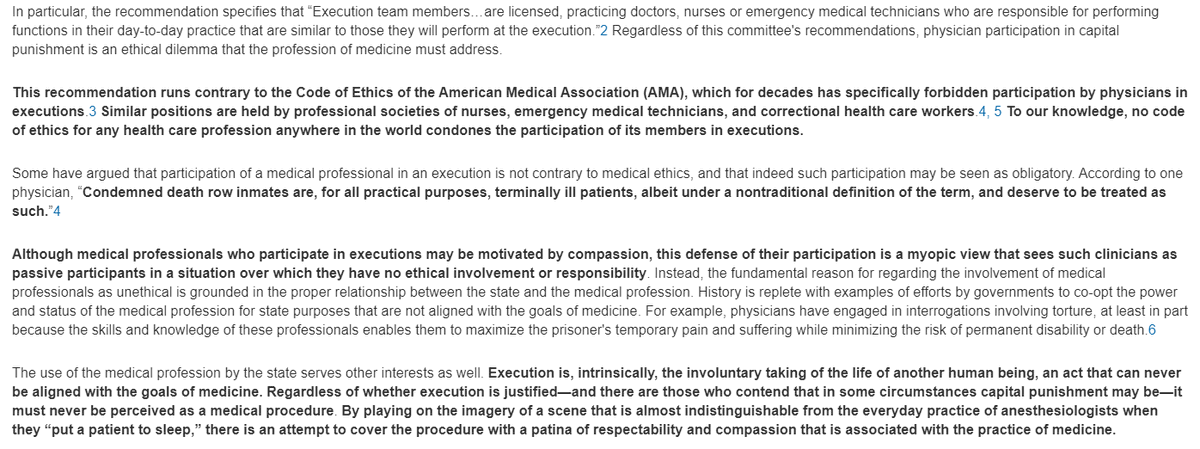

Some vilify the death penalty for a few criminals condemned publicly in a court of law

but defend destruction of millions of unborn children as a private issue 2 b decided between a woman & her abortionist

Some vilify the death penalty for a few criminals condemned publicly in a court of law

but defend destruction of millions of unborn children as a private issue 2 b decided between a woman & her abortionist

7. The tried & condemned will, before a crowd of somber witnesses, receive anesth b4 lethal inject'n, time of death recorded, body receiving a resp'ful burial.

Unborn child gets no anesthesia before being quietly dismembered in her mother's womb, her tiny parts heaped on a tray

Unborn child gets no anesthesia before being quietly dismembered in her mother's womb, her tiny parts heaped on a tray